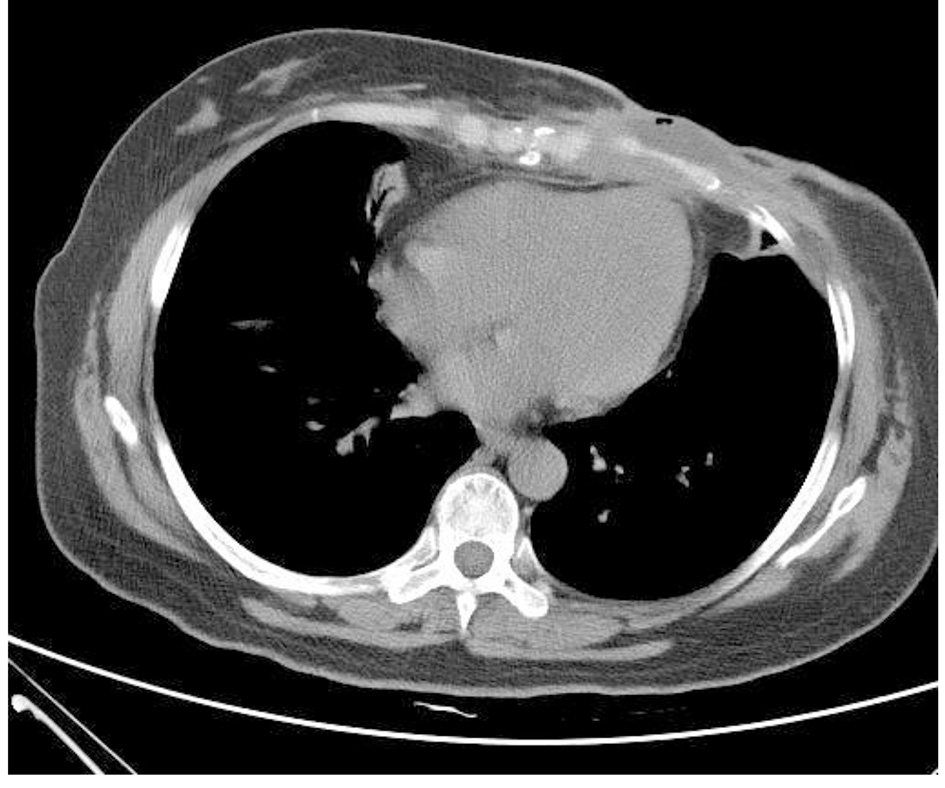

The chemotherapy of TEC (docetaxel + epirubicin + cyclophosphamide) was carried out for two rounds but the tumor did not shrink significantly. After the patient received the treatment of anti-infection and local and debridement, the pus embryo disappeared and no definite pathogenic bacteria were found during the repeated bacterial culture. However, the anabrosis did not shrink. On October 16, 2012, the radical operation of the left breast was performed successfully. On paraffin pathology, a malignant AME was found in the left breast and the tumor had infiltrated into the skin and pectoralis with the distance from the deep resection margin < 0.1 cm. No tumor embolus was seen in the vessel and 1/12 cancer cells of axillary lymph nodes had metastasized. Immunohistochemical examination showed ER (15% weakly +), PR (-), Ki-67 (30-40% +), C-erbB-2 (+), CK5/6 (+), p63 (partially +), CD10 (partially +), calponin (partially +) and CK8 (+). Auxiliary radiotherapy and chemotherapy were carried out. It was found that by the follow-up visit, the intractable subcutaneous hydrops appeared immediately after the operation (Fig. 2). According to the chest CT, bone destruction was seen in the sternum and the left fifth rib (Fig. 3). The patient died from pleural effusion and respiratory failure on August 23, 2014.

Figure 3.

Click for large image

Figure 3. Chest CT (on December 19, 2013): irregular low-density lesions were seen in front of sternum with the maximum cross-section of 4.3 × 2.9 cm. The border with the incrassated skin and the chest wall were not clear and the bone destruction was found in the sternum and the left fifth rib with the vague edge seen in part of costal cartilages.